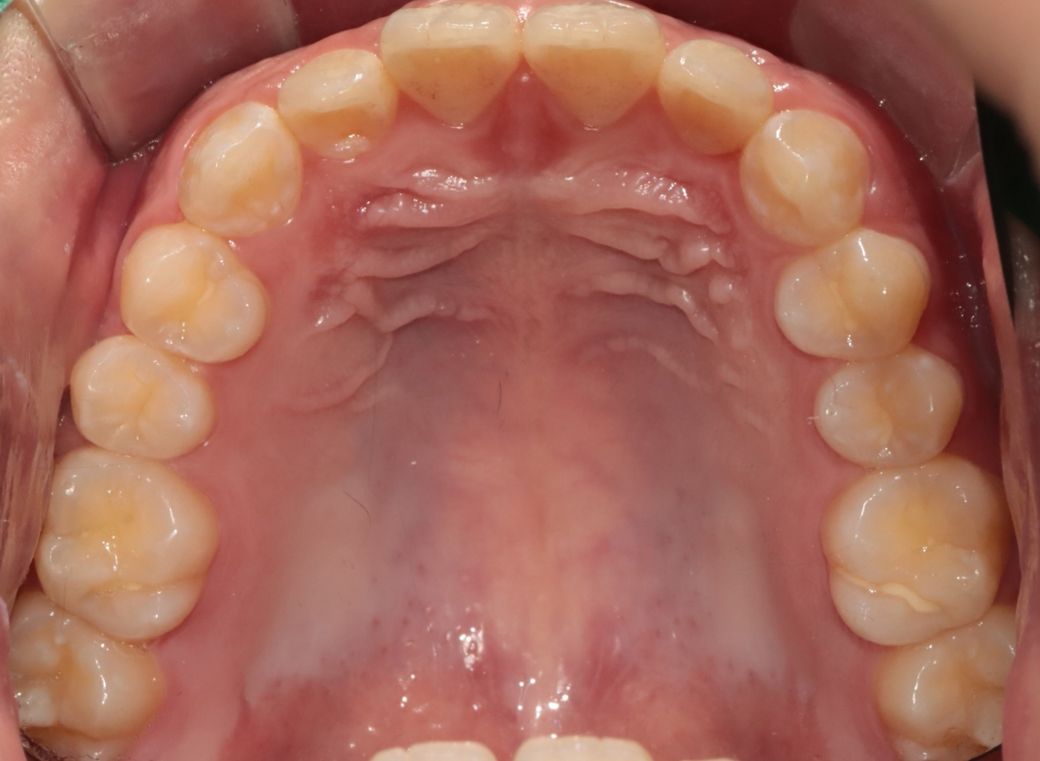

치아 앞니쪽에 반대교합이 있어서 분분교정할 생각인데 부분교정으로 치료가능해 보일까요?

앞니빼고 나머지는 괜찮아 보일까요?

윗니가 아랫니를 덮는 양또는 윗니가 앞으로 나온양이조금 적다고는 하는데 골격적 문제라 어쩔 수 없다는데 맞나요?

부분 교정으로도 어려워 보이며 전체 교정도 현재 증상을 개선하기가 쉽지 않아 보입니다. 워낙 다른 부위에 치열 상태는 나쁘지 않기 때문에 교정을 하더라도 현재 증상에 대한 개선이 어려울 수도 있어 보입니다. 또한 치열 배열 뿐만 아니라 골격적 문제가 동반되고 있어 골격적인 부분은 교정으로 수정할 수가 없습니다.

지금 정도의 골격적 부조화는 일반인들은 알아차리지 못하며 양악 등을 수술을 권하는 정도도 아닙니다.

사진상으로 보면 크게 문제가 있어보이지는 않습니다. 하지만, 기능상으로 문제가 있다면 교정을 하시거나 심미적개선을 원하신다면 교정을 하시면될것같아요.